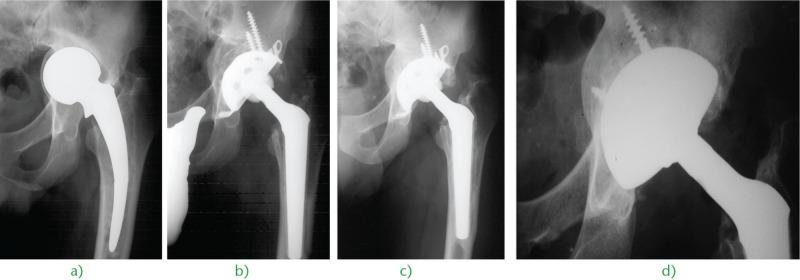

Acetabular bone loss is a relevant concern for surgeons dealing with a failed total hip arthroplasty.Since the femoral head is no longer available, allografts represent the first choice for most reconstructive solutions, either as a structural buttress or impacted bone chips.Even though fresh-frozen bone is firmly recommended for structural grafts, freeze-dried and/or irradiated bone may be used alternatively for impaction grafting. Indeed, there are some papers on freeze-dried or irradiated bone impaction grafting, but their number is limited, as is the number of cases.Xenografts do not represent a viable option based on the poor available evidence but bioactive bioceramics such as hydroxyapatite and biphasic calcium phosphates are suitable bone graft extenders or even substitutes for acetabular impaction grafting.Bone-marrow-derived mesenchymal stem cells and demineralised bone matrix seem to act as reliable bone graft enhancers, i.e. adjuvant therapies able to improve the biological performance of standard bone grafts or substitutes. Among these therapies, platelet-rich plasma and bone morphogenetic proteins need to be investigated further before any recommendations can be made. Cite this article: 2016;1:431-439. DOI:10.1302/2058-5241.160025.

髋臼骨缺损是髋关节置换失败的外科医生所面临的一个重要问题。由于股骨头已无法使用,同种异体骨移植成为大多数重建方案的首选,既可以作为结构性支撑物,也可以作为打压植骨的骨碎片。尽管强烈推荐使用新鲜冷冻骨进行结构性植骨,但冻干骨和/或辐照骨也可用于打压植骨。实际上,有一些关于冻干骨或辐照骨打压植骨的文献,但数量有限,病例数也不多。基于现有证据不足,异种骨移植不是一个可行的选择,但生物活性生物陶瓷,如羟基磷灰石和双相磷酸钙,是合适的骨移植增强剂,甚至可替代髋臼打压植骨。骨髓间充质干细胞和脱矿骨基质似乎是可靠的骨移植增强剂,即能够改善标准骨移植或替代物生物学性能的辅助治疗方法。在这些治疗方法中,富血小板血浆和骨形态发生蛋白在提出任何建议之前都需要进一步研究。引用本文:2016;1:431 - 439。DOI:10.1302/2058 - 5241.160025。